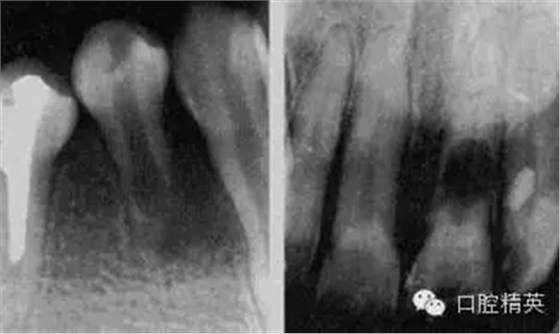

急性化膿性根尖周炎又稱急性牙槽膿腫,是由急性漿液性根尖周炎發(fā)展而來的,也可由慢性根尖周炎急性發(fā)作所致。急性化膿性根尖周炎在其發(fā)展過程中,因其膿液所在部位不同而劃分為根尖膿腫、骨膜下膿腫和黏膜下膿腫三個階段,主要癥狀為疼痛和腫脹,嚴(yán)重者伴有全身癥狀。

1.根尖膿腫 患牙有自發(fā)性、持續(xù)性、定位性劇烈跳痛,患牙浮起,咬合痛;檢查患牙叩痛、松動明顯,根尖部牙齦潮紅,有輕度捫痛。牙髓無活力。

2.骨膜下膿腫 患牙持續(xù)性劇烈跳痛達(dá)最高峰,更覺高起、松動,觸痛劇烈,相應(yīng)頜面部軟組織腫脹、壓痛,并伴有全身癥狀;檢查患牙為重度叩痛、Ⅲ°松動,牙齦紅腫,移行溝變平,壓痛明顯,捫診有深部波動感,牙髓無活力。

3.黏膜下膿腫 膿液已達(dá)黏膜下,疼痛減輕,全身癥狀緩解;檢查患牙叩痛(+)—(++),松動I°,根尖區(qū)黏膜腫脹呈半球形隆起,波動感明顯,牙髓無活力。